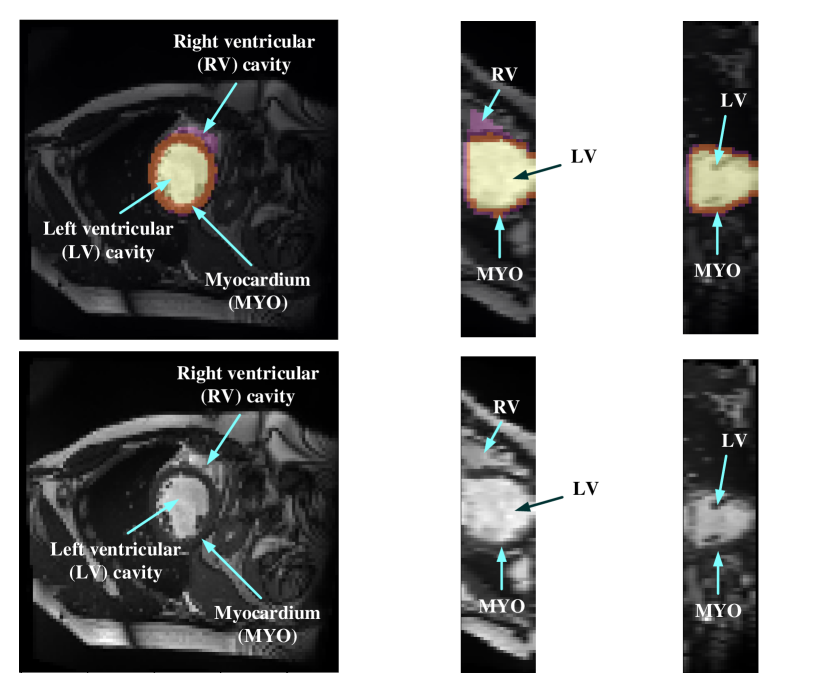

In order to evaluate the myocardial function, accurate segmentation of left ventricular (LV) cavity, right ventricular (RV) cavity, and myocardial (MYO) need to be acquired from the framework. Figure 1 shows the slices of typical CMR images of a patient at ED frame with and without ground truth mask along the each axis respectively. The label shows the ground truth of segment result for different parts of the CMR image.

Refer to caption

Figure 1: Structure illustration of a typical CMR image. Images above are the slices on z-axis, y-axis and x-axis respectively from patient 001 in the ACDC dataset at ED frame with mask, and the second row of figure are the raw CMR slices of patient 001.

Myocardial segmentation of CMR sequences has the following challenges. First, the contrast between myocardium and surrounding structures are low as shown in Figure 1. Second, the brightness heterogeneity in the left and right ventricular cavities due to blood flow [3]. Third, misleading structures such as papillary muscle have the same intensity and grayscale information as myocardium, which makes it hard to extract the accurate boundary. There are two approaches among existing works towards myocardium segmentation.